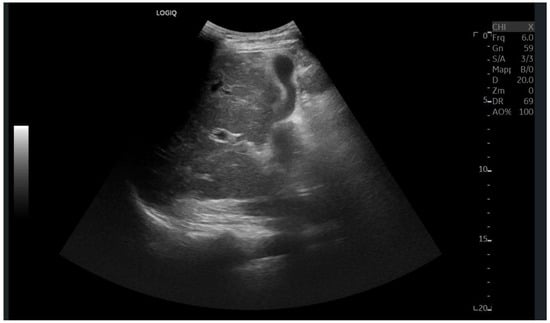

Ultrasound imaging is capable of identifying heterogeneous echotexture and hepatomegaly, which are early indicators of congestive hepatopathy [46]. Several studies have shown correlations between the extent of sonographic abnormalities and the severity of hepatic fibrosis or cirrhosis [36,47,48]. The most common ultrasound findings encompass a nodular hepatic surface, right-lobe volume reduction, smooth-to-rounded contour changes, and irregular outer profiles [49,50,51] (Figure 2). The echotexture appears granular and markedly heterogeneous, with hyperechogenic nodules of varying sizes [49,50,51] (Figure 3, Figure 4, Figure 5, Figure 6, Figure 7 and Figure 8).

Figure 6.

Diffuse echostructural change of the left lobe with a heterogeneous hyperechoic area measuring 89 × 81 mm.